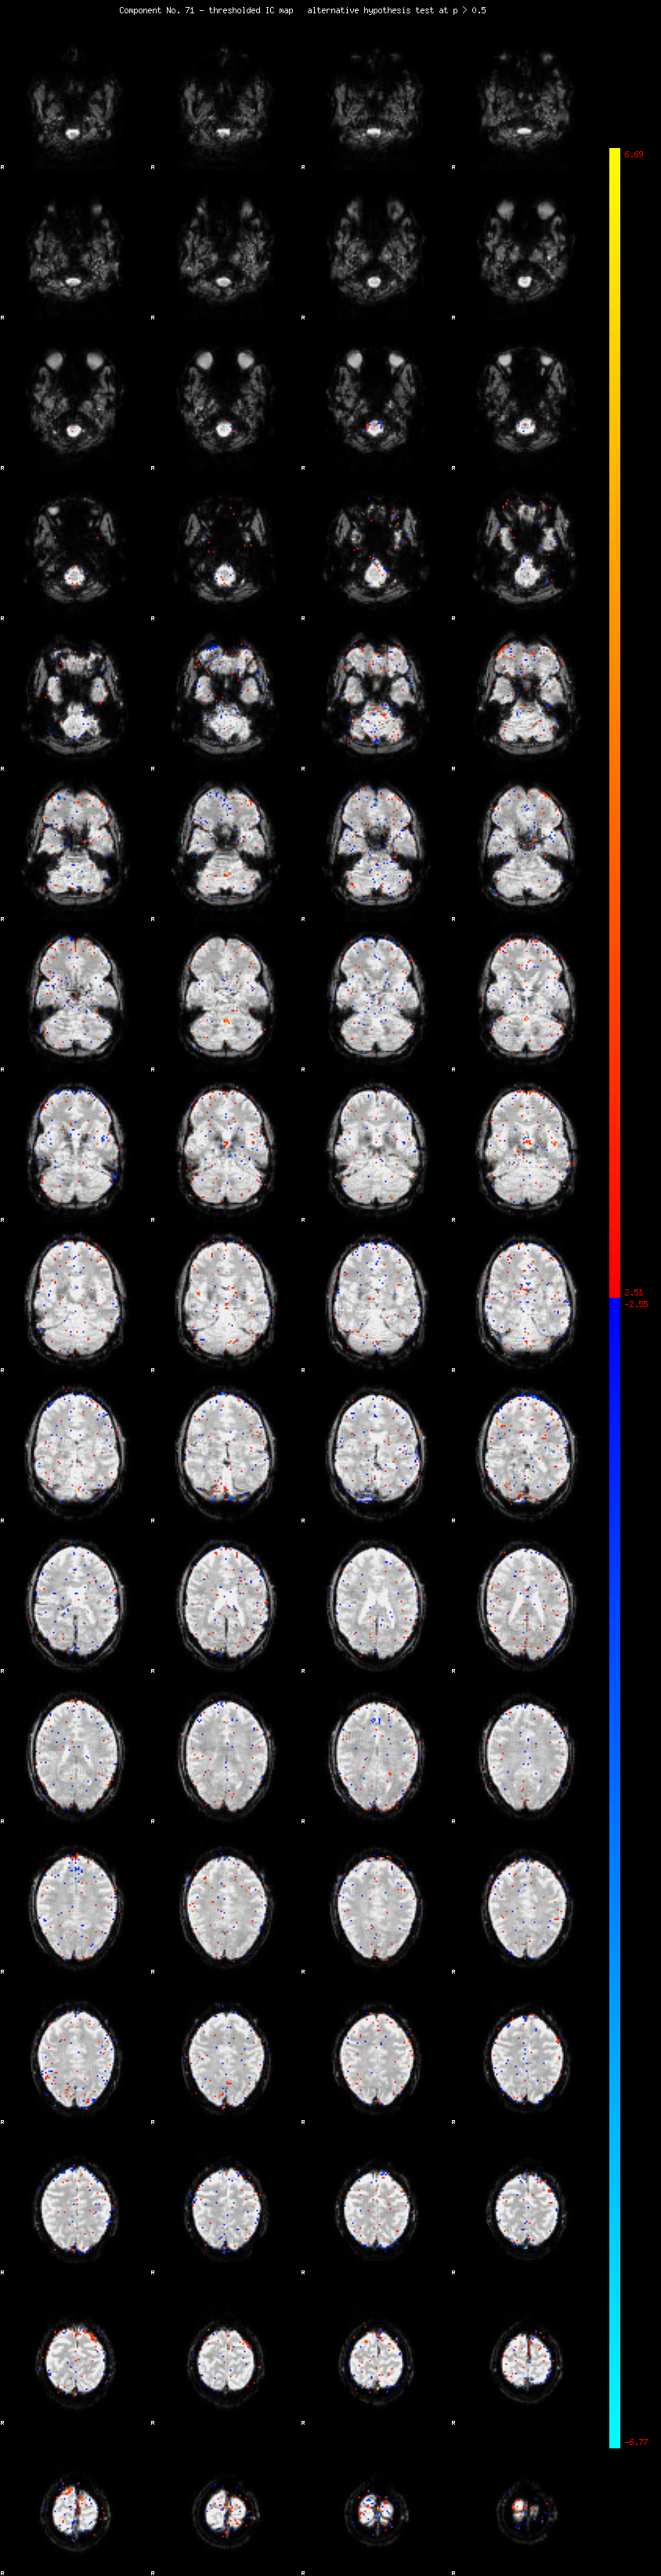

MELODIC Component 71

0.73 % of explained variance;     0.48 % of total variance

MMfit